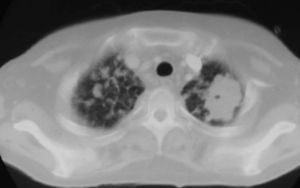

Fig. 2. Tomografía computarizada a la altura de los vértices pulmonares.